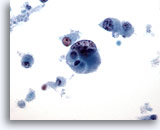

Figure 29

Breast FNA, Ductal carcinoma in situ.

Clusters of fairly bland tumor cells are noted. A vague impression of a fibrovascular core is noted in the cell group on the right. 40x

Figure 29

Breast FNA, Ductal carcinoma in situ.

Clusters of fairly bland tumor cells are noted. A vague impression of a fibrovascular core is noted in the cell group on the right.

40x